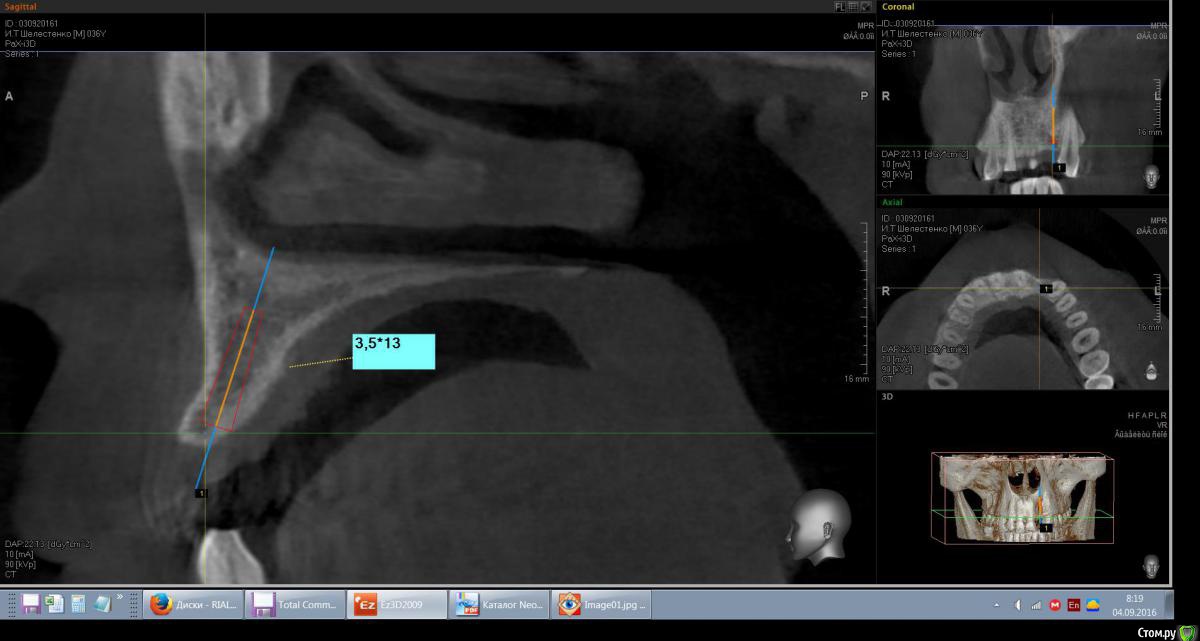

mann Опубликовано 4 сентября, 2016 Автор Поделиться Опубликовано 4 сентября, 2016 Доброе утро!Имеем такую ситуацию. Как лучше и правильно расположить имплант в данной ситуции? Ссылка на комментарий

red_butler Опубликовано 4 сентября, 2016 Поделиться Опубликовано 4 сентября, 2016 срезы выставлены не корректно 2 Ссылка на комментарий

red_butler Опубликовано 4 сентября, 2016 Поделиться Опубликовано 4 сентября, 2016 вот видите костное предложение на самом деле лучше. Только не нужно так небно ставить. Если сомневаетесь сделайте шаблон или пригласите на операцию ортопеда. И трансп добавьте. Ссылка на комментарий

mann Опубликовано 4 сентября, 2016 Автор Поделиться Опубликовано 4 сентября, 2016 И трансп добавьте. а что это?Т.е.правильным будет как на первом фото и угловой абатмент? Ссылка на комментарий

red_butler Опубликовано 4 сентября, 2016 Поделиться Опубликовано 4 сентября, 2016 а что это? трансплантат.Мне больше нравится позиция на втором снимке, только вестибулярнее и не так глубоко, и я бы ложе готовил эспандерами или чуток расщепился бы Ссылка на комментарий

kamranchick Опубликовано 4 сентября, 2016 Поделиться Опубликовано 4 сентября, 2016 а что это?Т.е.правильным будет как на первом фото и угловой абатмент?мясца с бугорка, если постарайтесь то можно даже прямой абатмент сделать. при позиционировании смотрите на нижние антагонисты Ссылка на комментарий